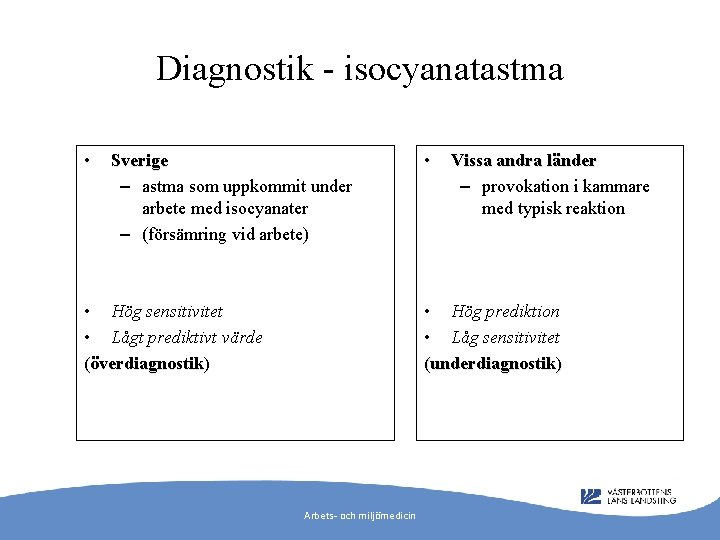

Diagnostik - isocyanatastma • Sverige – astma som uppkommit under arbete med isocyanater – (försämring vid arbete) • Hög sensitivitet • Lågt prediktivt värde (överdiagnostik) • Vissa andra länder – provokation i kammare med typisk reaktion • Hög prediktion • Låg sensitivitet (underdiagnostik) Arbets- och miljömedicin